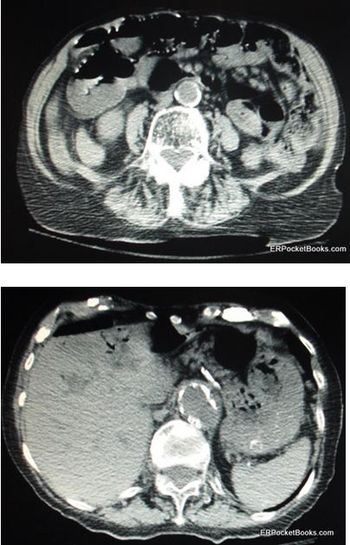

At risk for mesenteric ischemia-an uncommon but feared cause of abdominal pain-are the elderly and chronically ill.